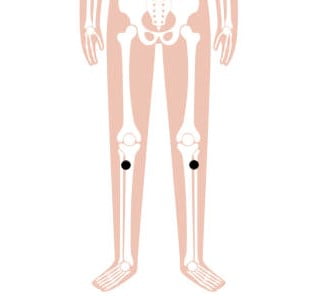

1. Zusanli

Een specifiek acupunctuurpunt, Maag 36 (ST36), onder de knie, kan gewichtsverlies bevorderen. ST36 staat in het Chinees bekend als Zusanli en betekent letterlijk ‘drie beenmijl’. Traditioneel gezien geeft het behandelen van dit punt de behandelde persoon een energieboost. Daardoor kan deze persoon aan het eind van de dag nog eens vijf kilometer extra konden lopen. In de traditionele Chinese geneeskunde heeft dit punt vele toepassingen, waaronder het wordt gebruikt voor vermoeidheid, zwakte, verkoudheid en een verminderde spijsvertering.

4. Fenglong

Fenglong, ofwel Maag 40 (ST40), wiens Chinese naam zich vertaalt naar ‘overvloedige overvloed’, is een punt dat zeer geschikt is om damp af te voeren. In TCM is overmatige gewichtstoename meestal te wijten aan de ophoping van damp. Dit acupunctuurpunt reguleert voornamelijk het maagdarmkanaal, verwijdert lichaamsvloeistoffen, voedt de milt en de nieren, brengt Qi (energie) en bloed in evenwicht. Dit zorgt er dan vervolgens voor dat zwaarlijvige mensen gewicht kunnen verliezen.